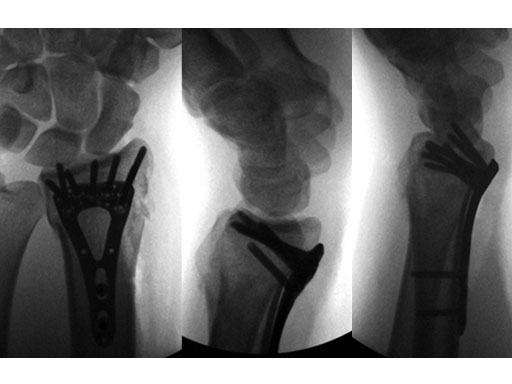

Fig 3ac Immediate postoperative x-rays.